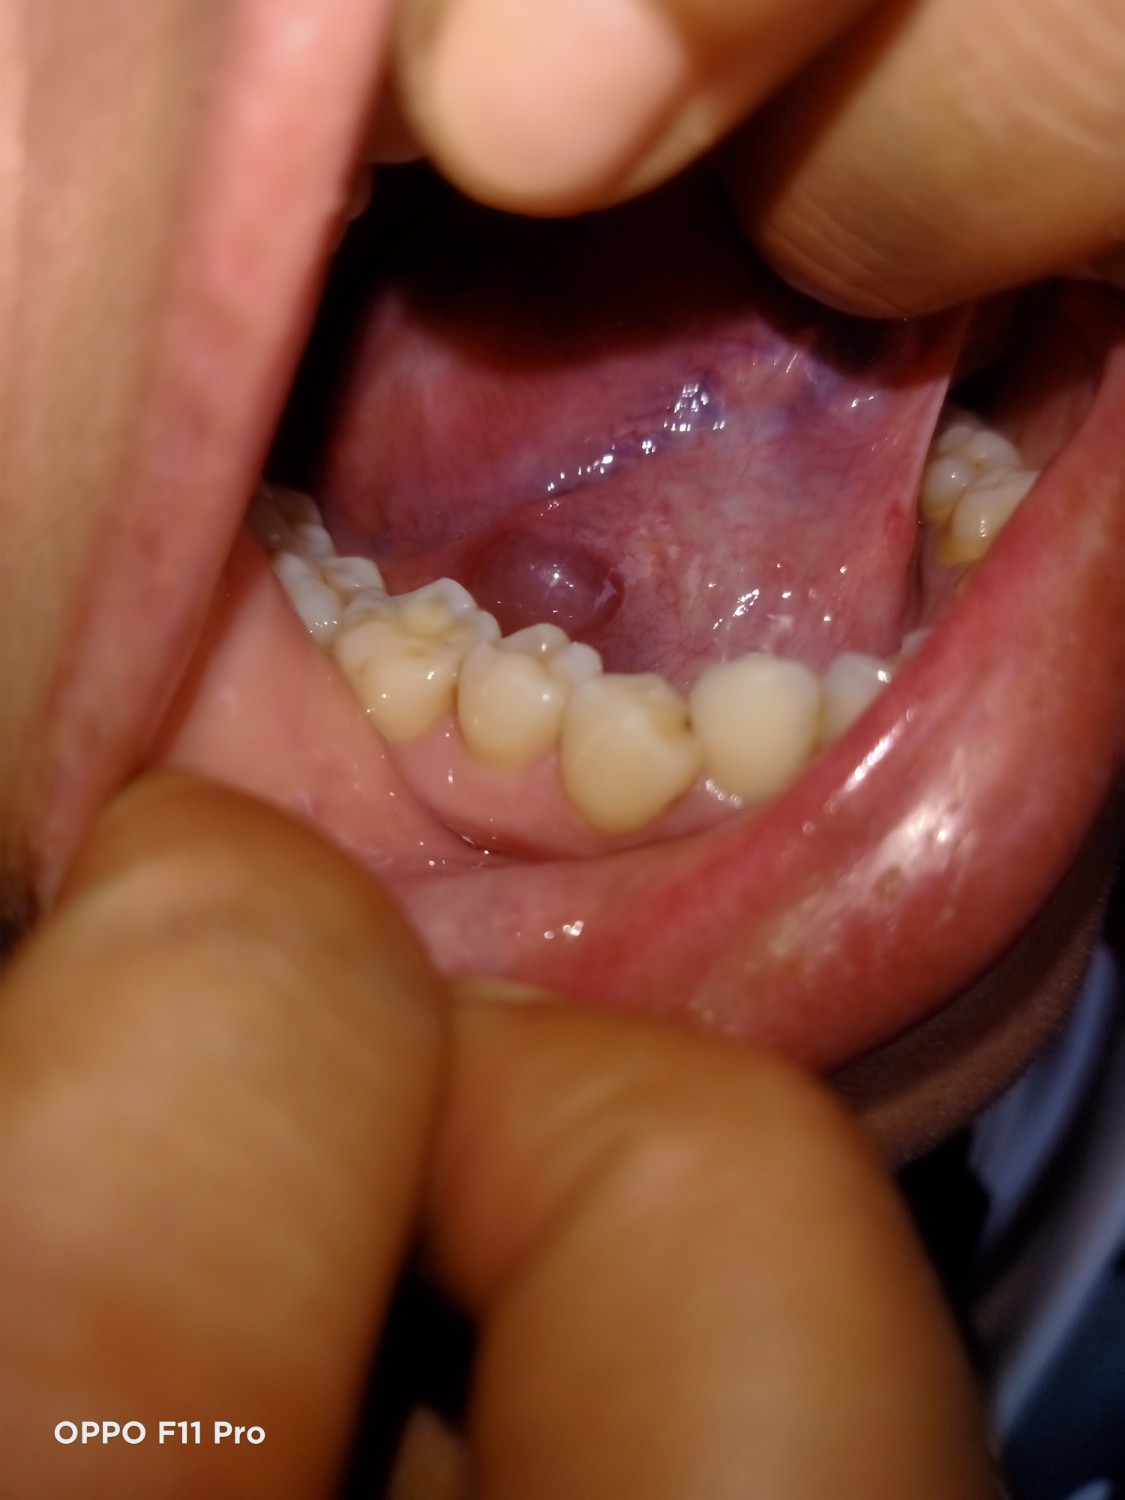

โรคใต้ลิ้นบวม

สอบถามผู้รู้ค่ะ พอดีอยู่ๆใต้ลิ้นบวมขึ้นคล้ายถุงน้ำน้ำขนาดใหญ่ไม่เจ็บมาก ไปหาหมอที่ รพ.บอกว่าไม่เป็นไรแต่กลับมาบ้านรู้สึกว่ามันบวมใหญ่ขึ้นและเริ่มบวมที่ลำคอ เวลาก

ลืนอะไรจะรู้สึกหน่วงๆที่คอ

เรารู้สึกกังวลมากค่ะ สอบถามผู้รู้หน่อยค่ะ

มีภาพให้ดูด้วยนะคะอาจจะไม่ค่อยชัด